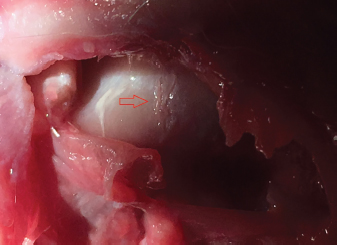

Fig. 7. Iatrogenic laceration of the cartilage of the humeral head (red arrow).